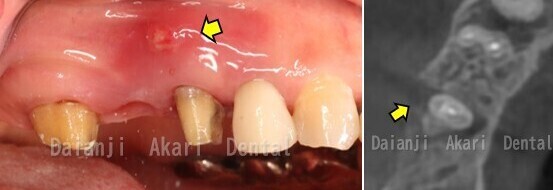

症例2

右上の奥歯が腫れていた患者様です。

初診時(上図)歯肉は腫れており、膿が出ていました(矢印)。

CT画像から歯の周囲の骨が溶けていることがわかりました(矢印)。

歯根破折のため、腫れている歯を抜歯し、骨造成を行いました。

骨や歯肉の治癒を待ってから2本インプラント治療を行いました(下図)。